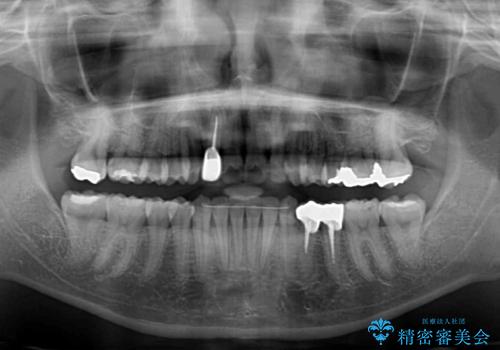

神経を取り除かれている歯3本以外にも虫歯が認められたため、事前に処置を行い、インビザラインにて矯正治療を行うこととしました。

神経が取り除かれている歯は、クラウンによる補綴治療が必要であるため、矯正治療後にオールセラミッククラウンにて補綴治療を行うこととしました。

歯磨きしやすくなるとともに、飛び出していた前歯も引っ込めて整えることができました。